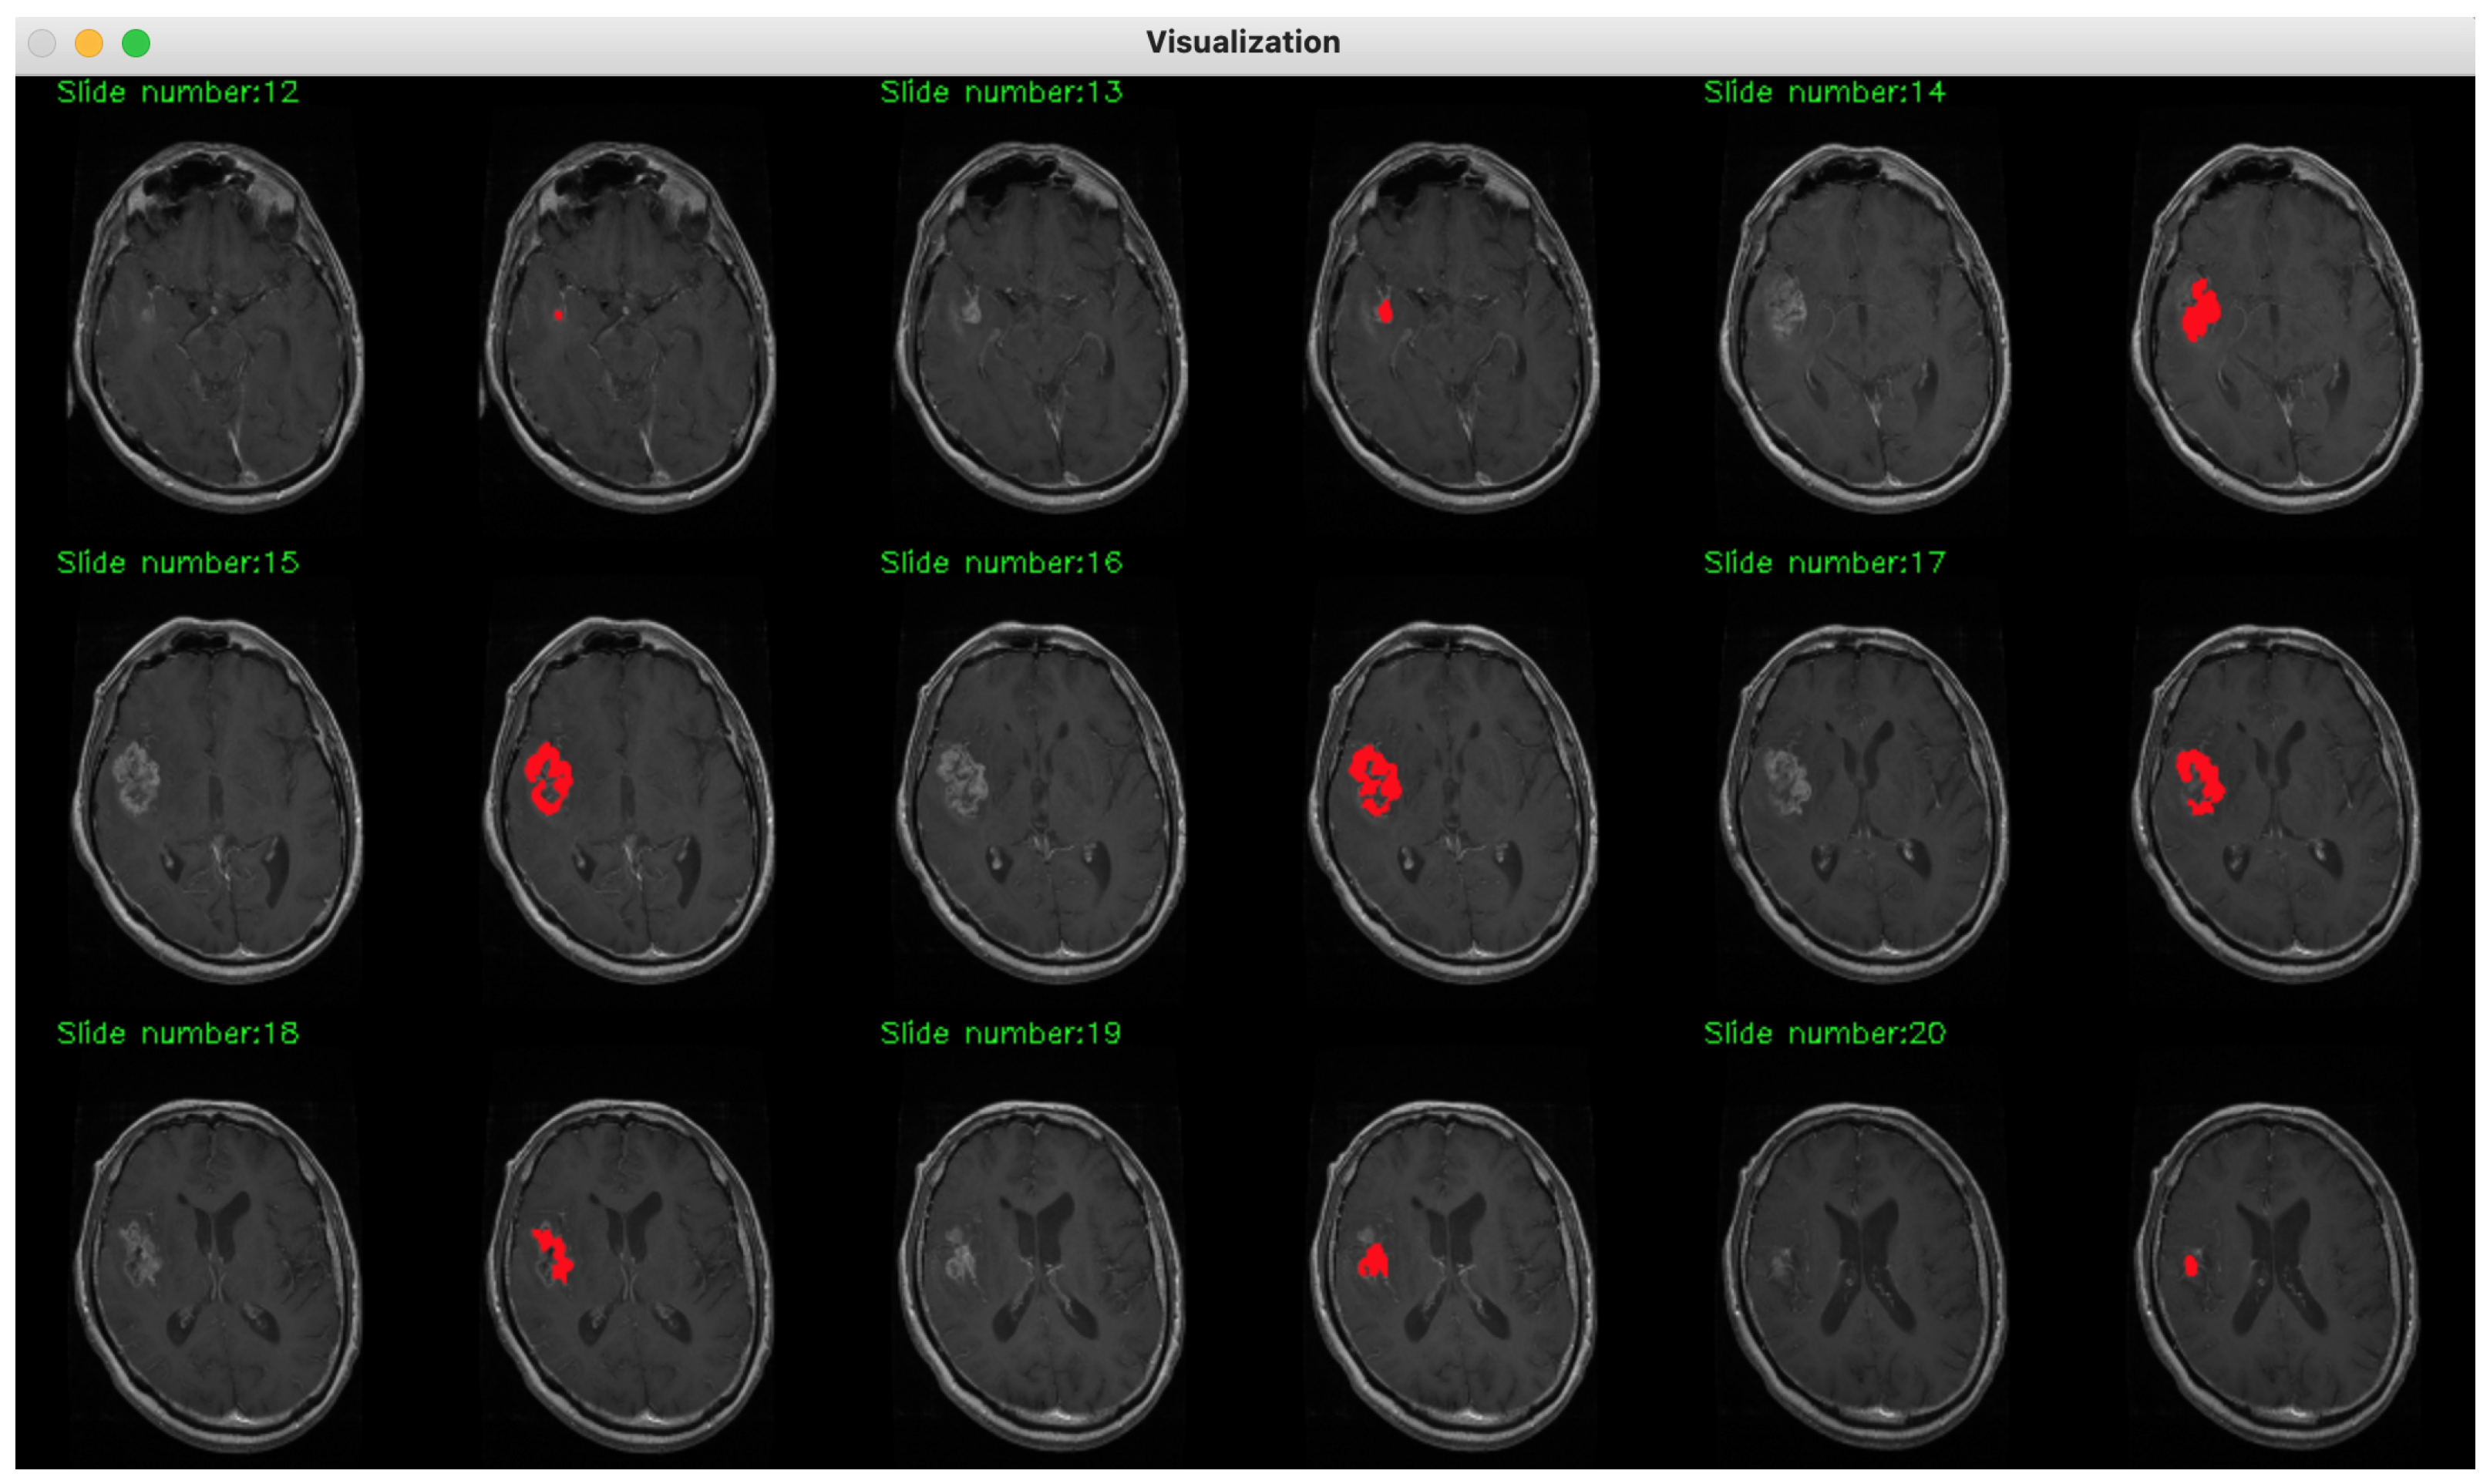

2. Method Description

3. Database Description

4. Experimental Assessment